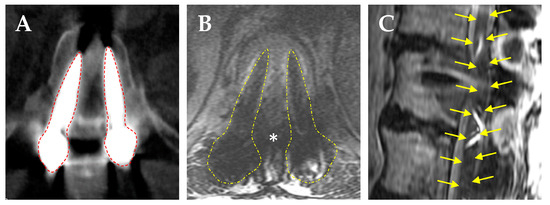

- De Almeida, R.A.A.; Ghia, A.J.; Amini, B.; Wang, C.; Alvarez-Breckenridge, C.A.; Li, J.; Rhines, L.D.; Tom, M.C.; North, R.Y.; Beckham, T.H.; et al. Quantification of MRI Artifacts in Carbon Fiber Reinforced Polyetheretherketone Thoracolumbar Pedicle Screw Constructs prior to Spinal Stereotactic Radiosurgery. Pr. Pract. Radiat. Oncol. 2024, 14, 103–111. [Google Scholar] [CrossRef] [PubMed]

- Kalasauskas, D.; Serrano, L.; Selbach, M.; Stockinger, M.; Keric, N.; Brockmann, M.A.; Ringel, F. Qualitative Assessment of Titanium versus Carbon Fiber/Polyetheretherketone Pedicle Screw-Related Artifacts: A Cadaveric Study. World Neurosurg. 2022, 166, e155–e162. [Google Scholar] [CrossRef]

- Fleege, C.; Makowski, M.; Rauschmann, M.; Fraunhoffer, K.L.; Fennema, P.; Arabmotlagh, M.; Rickert, M. Carbon fiber-reinforced pedicle screws reduce artifacts in magnetic resonance imaging of patients with lumbar spondylodesis. Sci. Rep. 2020, 10, 16094. [Google Scholar] [CrossRef]